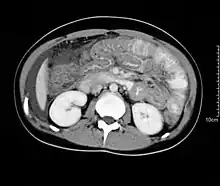

H&E Stain: Dense Eosinophilic infiltration of gastro-duodenal wall | |

Hypereosinophilia, the hallmark of allergic response, may be absent in up to 20% of patients, but hypoalbuminaemia and other abnormalities suggestive of malabsorption may be present. CT scans may show nodular and irregular thickening of the folds in the distal stomach and proximal small bowel, but these findings can also be present in other conditions like Crohn's disease and lymphoma.

The endoscopic appearance in eosinophilic gastroenteritis is nonspecific; it includes erythematous, friable, nodular, and occasional ulcerative changes.[21] Sometimes diffuse inflammation results in complete loss of villi, involvement of multiple layers, submucosal oedema and fibrosis.[22][23]

Definitive diagnosis involves histological evidence of eosinophilic infiltration in biopsy slides. Microscopy reveals >20 eosinophils per high power field.[12][20] Infiltration is often patchy, can be missed and laparoscopic full thickness biopsy may be required.